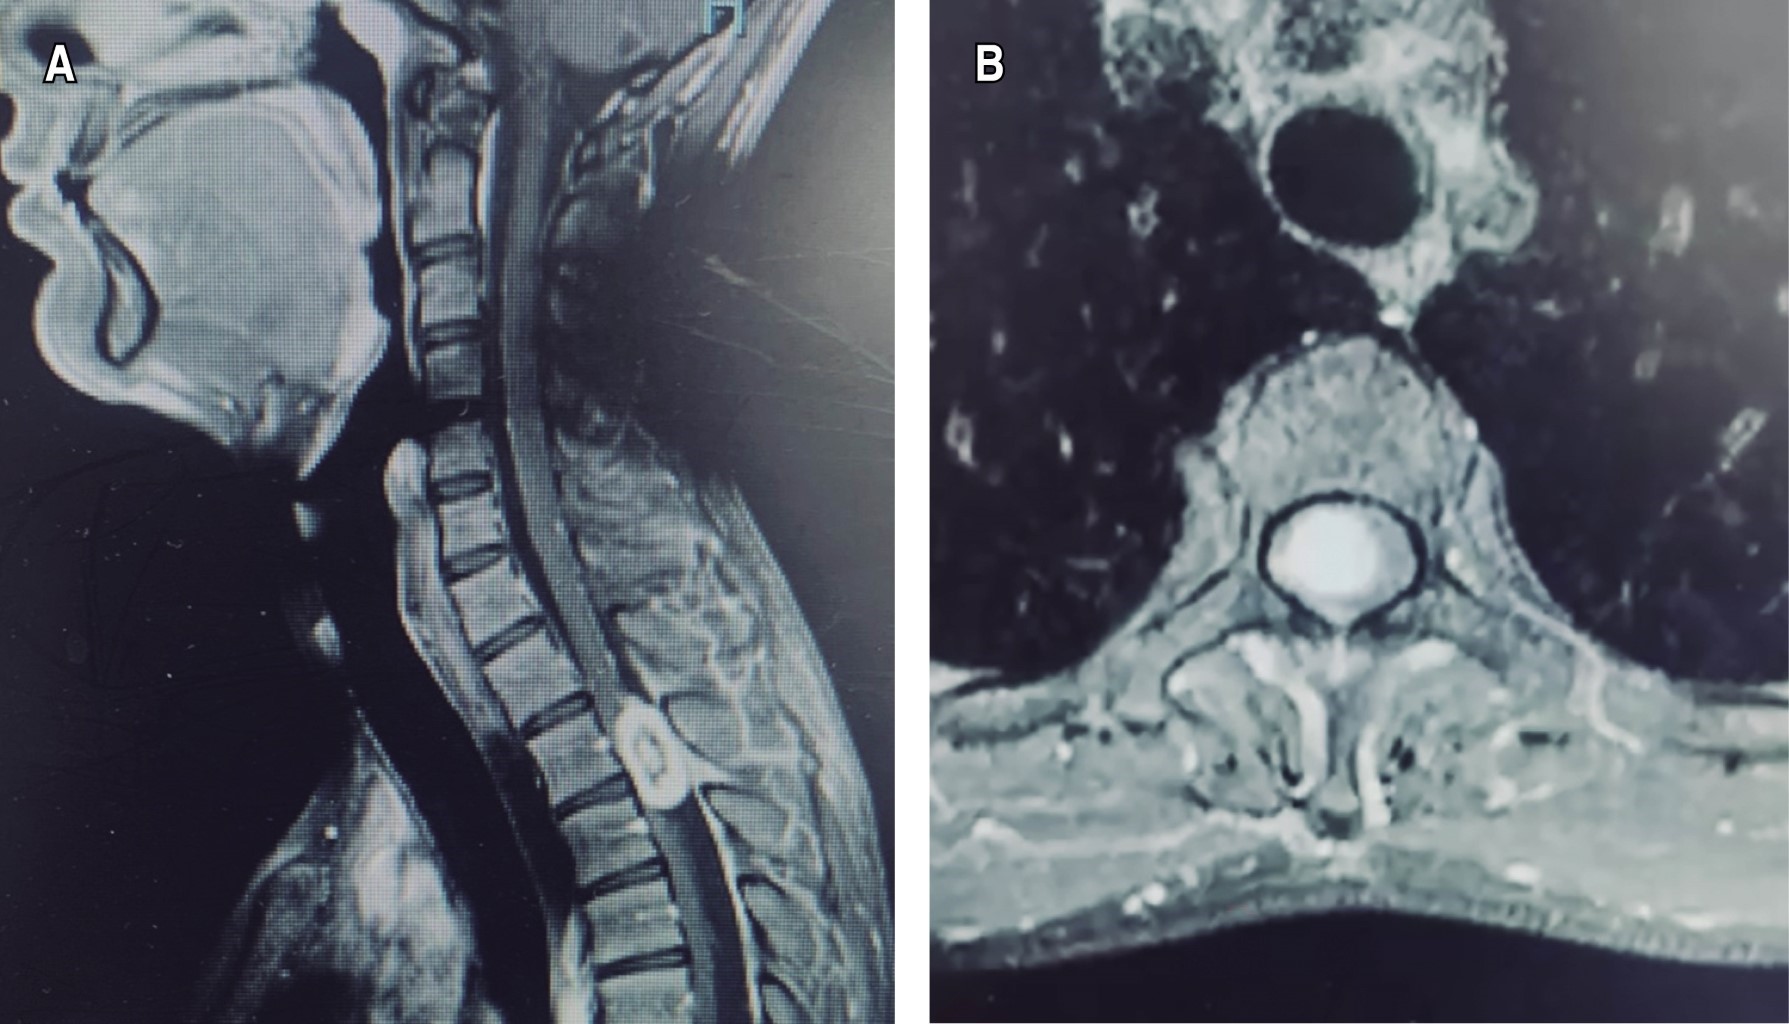

La resonancia magnética contrastada reveló una lesión intradural extramedular a nivel de la columna torácica en los niveles T2-T3, isointensa en T1, hiperintensa en T2 y con realce al gadolinio (Figura 1).

La resonancia magnética es el estudio de elección para el diagnóstico de las lesiones espinales intradurales, siendo la resonancia magnética contrastada el estudio de elección para estos tumores. Los meningiomas, schwannomas y ependimomas presentan características similares en la resonancia magnética, lo que hace difícil el diferenciarlos basándose sólo en las imágenes. Las imágenes ponderadas en T1 son isointensas, las ponderadas en T2 son hiperintensas y con la aplicación de medio de contraste presentan un realce homogéneo. Aunque los meningiomas suelen mostrar una "cola dural" como dato imagenológico característico, esto no se ve de manera consistente.19